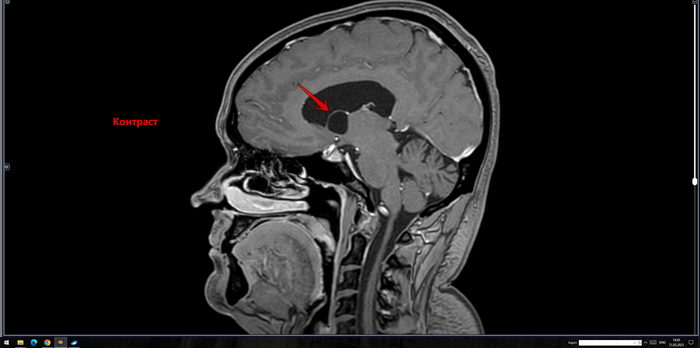

В расширенном турецком седле определяется солидное объемное образование неоднородно повышенного МР-сигнала на Т2 ВИ, размерами до 30 х 25 х 19 мм, неоднородно копит контраст. Образование распространяется в область кавернозных синусов по ходу С5 С6 сегментов внутренних сонных артерий, муфтообразно охватывая их до 70% окружности справа и до 50% окружности слева. Внутренние сонные артерии на уровне образования не сужены. Образование интимно прилежит к задним базальным отделам прямых извилин и зрительному перекресту, больше справа, без его оттеснения. Воронка гипофиза утолщена, отклонена вправо.На этом фоне нормальная структура гипофиза четко не определяется, вероятно, оттеснена вправо и кзади.

Заключение: МР- картина образования гипофиза, соответствует макроаденоме средних размеров с супра- и латероселлярным характером роста. Рек-но: конс. нейрохирурга.